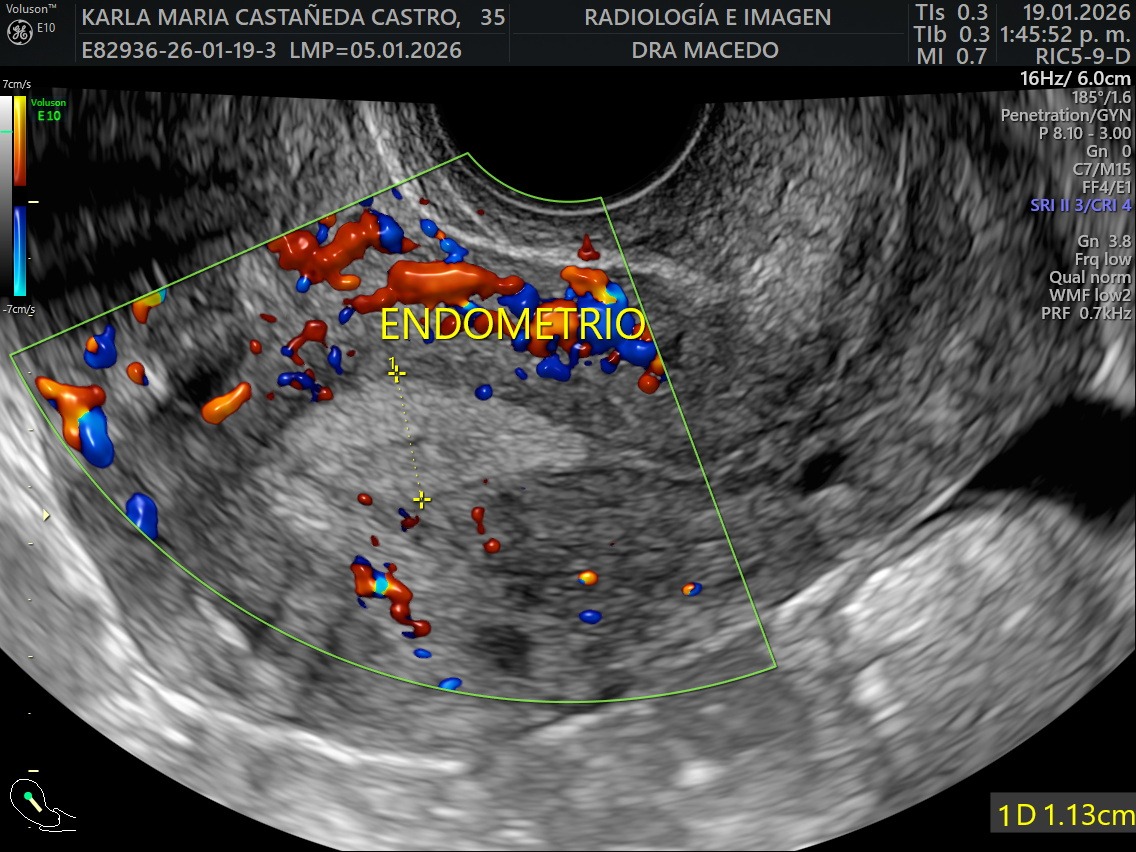

I was recently diagnosed with 16 large uterine fibroid tumors (myomas). My doctors have told me that I need immediate major surgery to remove them. The procedure I will undergo is an Open Abdominal Myomectomy, along with a biopsy to ensure there are no cancerous cells. I will also need to stay in the hospital for approximately five days during recovery. Although even if the tumors are benign, they are putting extreme pressure on my surrounding organs causing significant pain, bleeding, fatigue, and health related issues on a daily basis.

Recientemente me diagnosticaron 16 tumores de fibromas uterinos (miomas). Mis médicos me han informado que necesito una cirugía mayor inmediata. El procedimiento al que me someteré es una miomectomía abdominal abierta, junto con una biopsia para asegurar que no haya células cancerosas. También necesitaré permanecer en el hospital aproximadamente cinco días durante la recuperación. Aunque los tumores de miomas parecen ser benignos, están ejerciendo una presión extrema sobre mis órganos que los rodean, causando dolor significativo, sangrado, fatiga y problemas de salud a diario.